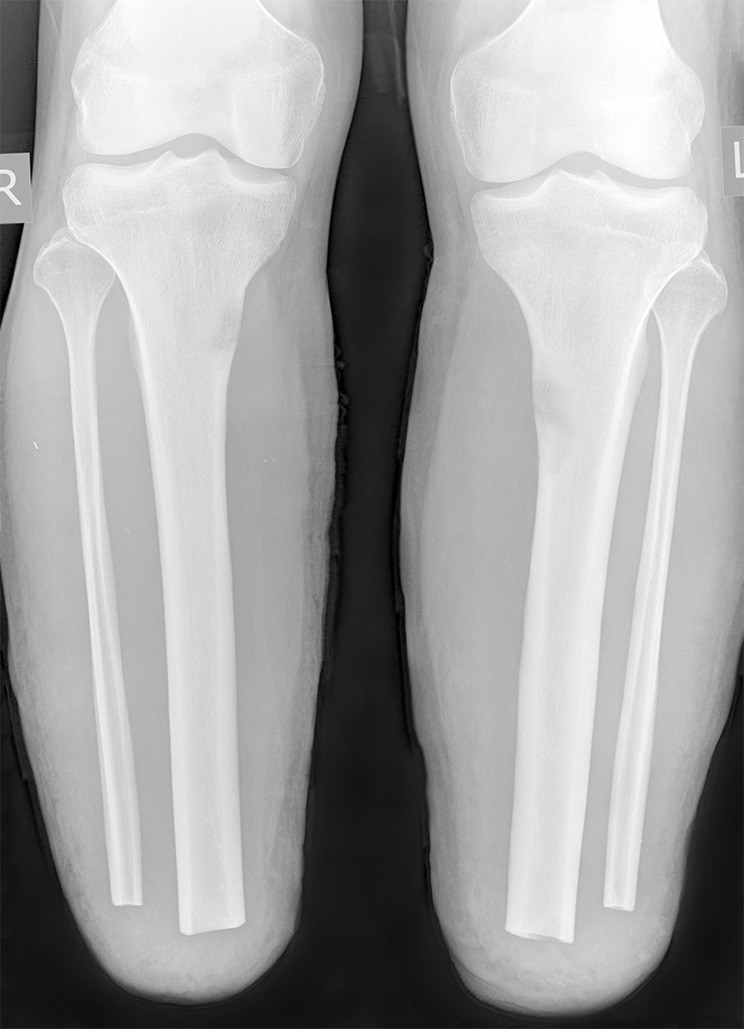

Aim: To familiarize specialists with the possibility of simultaneous bilateral stress fractures of amputation residual limbs resulting from intensive loads and poor-quality prosthetics causing chronic compartment syndrome. A case of bilateral stress fractures of the tibia in a 28-year-old male military serviceman with paired transtibial amputation is presented. The fractures occurred in the process of active exploration of poorly fitting prostheses, complicated by chronic compartment syndrome that masked the clinical picture.

Techniques: Radiography, ultrasound, blood biochemistry, measurement of subfascial pressure.

Outcomes: After treatment, the phenomena of compartment syndrome disappeared, stress fractures healed, new receiving sleeves of prostheses were made, gradual dosed loads were started. 7 months after the diagnosis of stress fractures and compartment syndrome, the patient started using the prosthesis without aids. Examined 18 months later. Worked as a warehouse manager, walking an average of 4 km per day.

Conclusion: With complaints from the patient with an amputation stump of muscle and bone pain that appeared after exercise, passed after rest, and reparative reaction detected on radiographs, functional overstrain of the bone should be suspected, which can potentially lead to a stress fracture. The causes of stress fractures in the patient were acute overstrain of the bone tissue during prosthesis development, noncompliance with the loading and resting regimes, and local disturbance of the bone blood supply due to the narrowed rigid socket of the prosthesis. Stress fractures of the bone tissue of the amputation stump contain elements of insufficiency and fatigue. Chronic compartment syndrome may exacerbate and mask the stress fracture.